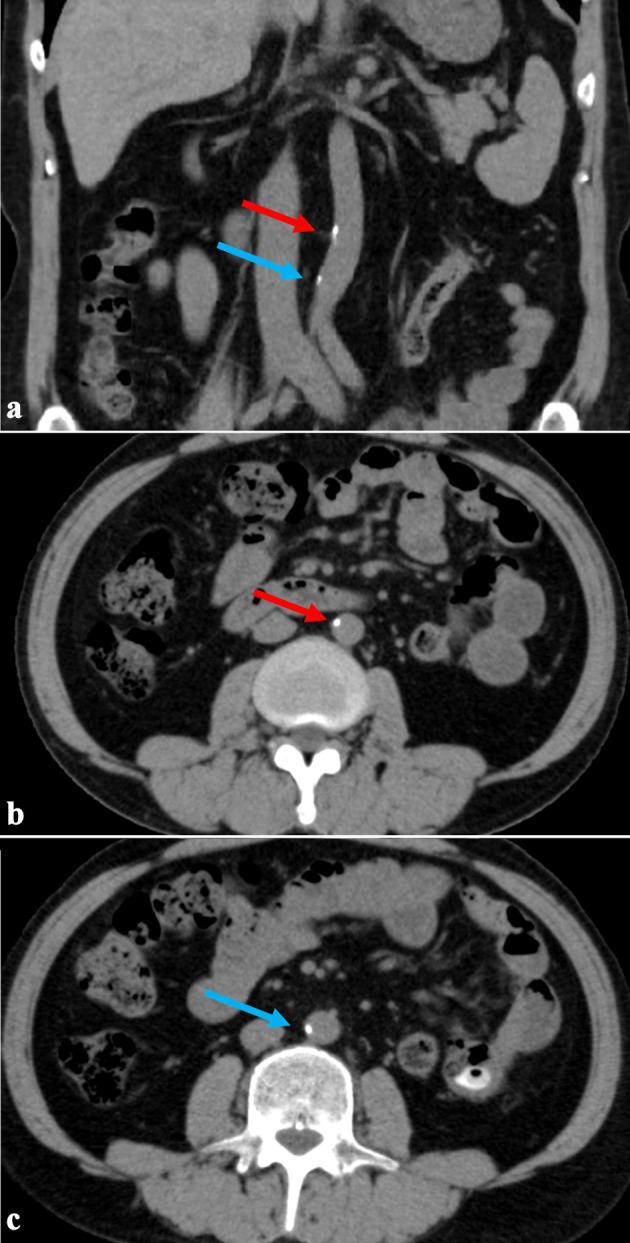

Vascular calcification is common in dialysis patients and is severely associated with cardiovascular morbidity and mortality. They have mineral metabolism disorders, which are considered to promote vascular calcification. In addition, hypertension and malnutrition, both prevalent in dialysis patients, are also considered risk factors contributing to vascular calcification. Our clinic has implemented extended-hours hemodialysis without dietary restrictions to solve the problems of hypertension and malnutrition in dialysis patients. We report a case where aortic calcification was slight despite 34 years of long-term dialysis. He underwent his first computed tomography (CT) scan of the chest and abdomen 29 years after initiating hemodialysis to evaluate his kidney transplant. The abdominal aortic calcification index 29 years after initiating dialysis was low at 5.8%, and even after 5 years, it was only 6.7%. The coronary artery calcification score was moderate at 214.0, but the degree of vascular calcification appeared milder than in conventional dialysis patients. His dialysis modality is unique. He began extended-hours hemodialysis without dietary restrictions 1.5 years after his transfer to our clinic, extending his dialysis time to 6 h. He gradually increased it to 10 h, and the dietary restriction was significantly relaxed. Moreover, he has been undergoing this treatment for about 26 years. His muscle mass increased, and his nutritional status remained adequate. The mean serum phosphorus and calcium levels were within the normal range (5.4 ± 0.5 mg/dL and 8.8 ± 0.3 mg/dL), and the calcium-based phosphate binder was successfully reduced and eventually discontinued. Furthermore, the blood pressure normalized without the use of antihypertensive medications. These may have removed some of the risk factors for vascular calcification. Recent studies suggest that extended-hours hemodialysis without dietary restrictions significantly lowers calciprotein particle levels, a risk factor for vascular calcification, compared to conventional dialysis. In conclusion, extended-hours hemodialysis without dietary restrictions may reduce the risk of vascular calcification by improving control of malnutrition, hypertension, and mineral metabolism.